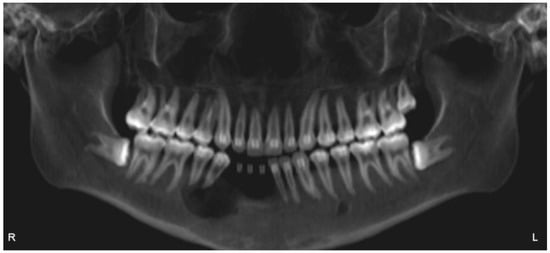

2.1. Case 1